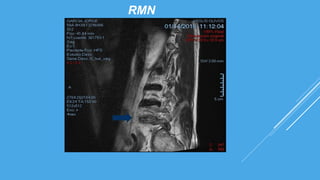

RMN

PROTRUSIÓN DISCAL ANTERIOR A NIVEL L1-L5, A NIVEL DE L4-L5 EXTRUSIÓN

DISCAL ANTERIOR CON OBSTRUCCIÓN NEUROFORAMIDAL CON MIGRACIÓN

CAUDAL BILATERAL QUE CONTACTA CON ESPACIO SUBDURAL ANTERIOR AL IGUAL

QUE A NIVEL DE L2-L3, SE VISUALIZA DISTESIS ANTERIOR A NIVEL DE L3 SOBRE L4

Y L4 SOBRE L5.